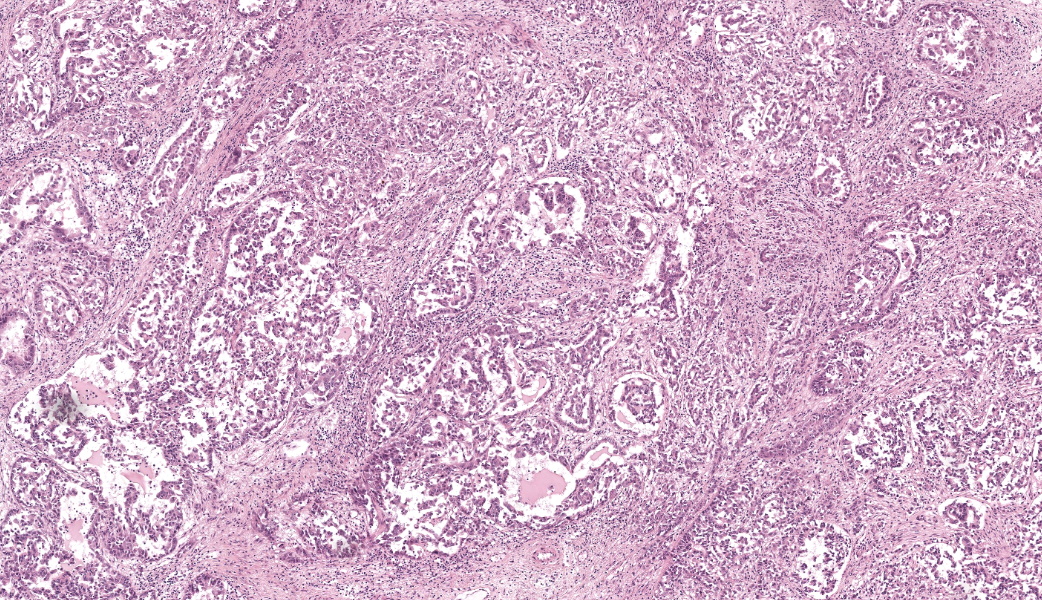

Microscopic Description:

Extending from and infiltrating the omentum is an unencapsulated, poorly demarcated, moderately cellular neoplasm composed of cuboidal to polygonal cells arranged in acini, tubules and nests, and more rarely micropapillary projections, on a moderate fibrovascular stroma. Neoplastic cells have variably distinct cell borders, an abundant amount of granular, eosinophilic and occasionally indistinctly vacuolated cytoplasm, and a pleomorphic, centrally placed nucleus with finely stippled to marginated chromatin and up to 3, occasionally very large distinct magenta nucleoli. There is marked anisocytosis and anisokaryosis, and 21 mitotic figures in 2.37mm2 – equivalent of 10 high power fields (40x obj); these are occasionally bizarre. There are occasional multinucleated neoplastic cells with up to 3 nuclei which occasionally compress and occasional apoptotic bodies are seen. Multifocally, neoplastic stroma contains minimal extravasations of erythrocytes (haemorrhage), and there are multifocal mild infiltrations of deform adjacent nuclei (nuclear molding).

There is occasional single cell necrosis, andmainly mature small lymphocytes, some plasma cells, and fewer neutrophils. Blood vessels are multifocally moderately congested and are often lined by plump (reactive) endothelium.

This third case was challenging due to the epithelioid nature of this mesothelioma. Most conference participants were readily able to reach a diagnosis of “carcinoma” or “adenocarcinoma” and many listed epithelioid mesothelioma as a differential. Tissue identification was challenging and only the most experienced participants felt confident calling it omentum based off the HE secttion. The features described by these participants that clued them in to “omentum” included a nodular “string of pearls” subgross appearance, the composition of a highly vascular fibroadipose tissue, and the wherewithal to remember that the omentum exists in the first place, which can be challenging in and of itself some days. The contributor provided a succinct, eloquent write-up on mesotheliomas and their classifications, which were covered during the conference discussion.